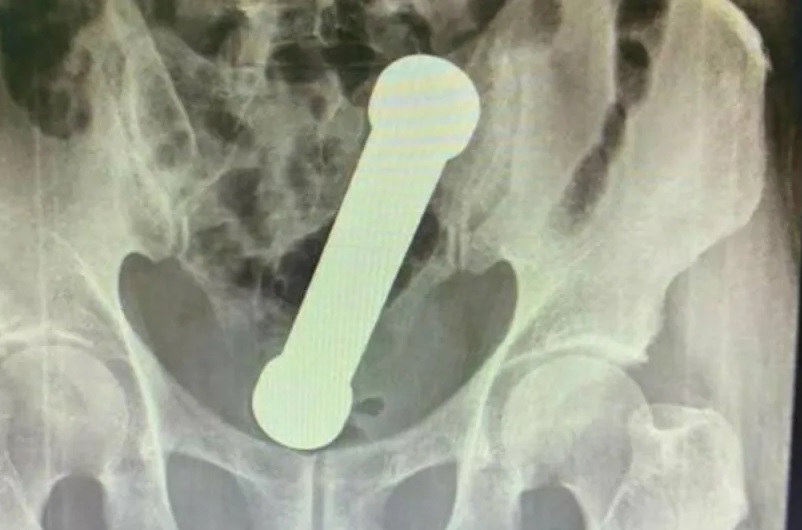

O rapaz foi submetido a uma bateria de exames, incluindo um raio-X, que mostrou a presença do haltere de 2 kg. O objeto de cerca de 20 centímetros estava entre o reto e o intestino grosso do paciente.

Após o causador do problema ser diagnosticado, o paciente admitiu que havia introduzido o objeto para prazer sexual.